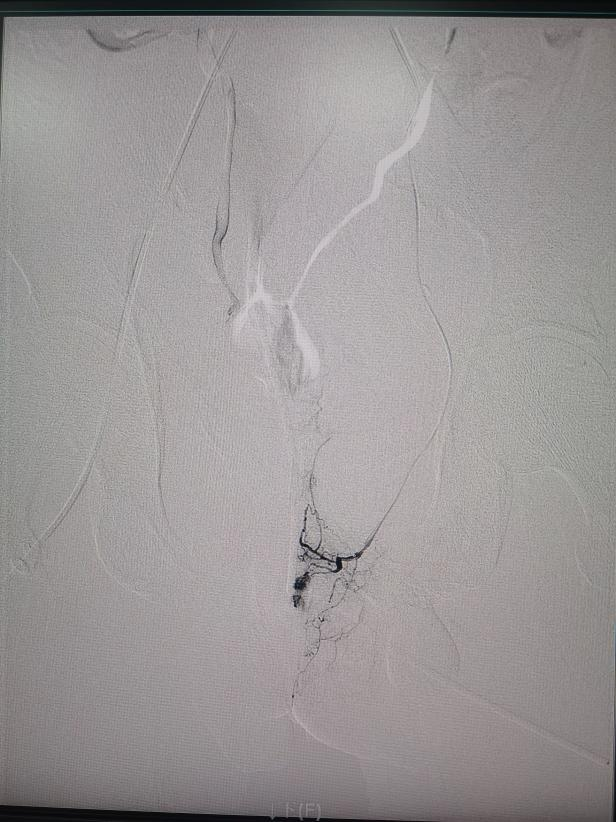

本次造影提示

左侧髂内动脉远端分支有造影剂外溢

术前造影提示动脉出血

手术中,介入治疗医学中心主任罗阳带领医师林杰、李思刚,借助DSA影像实时引导,精准锁定左侧髂内动脉远端分支的出血点。

面对骨盆骨折后复杂的血管情况,专家们精细操作,如 “穿针引线” 般直达出血分支,用明胶海绵颗粒成功堵住 “漏水口”!术后造影显示,靶血管血流截断,外溢征象完全消失。出血完全停止,手术非常成功!